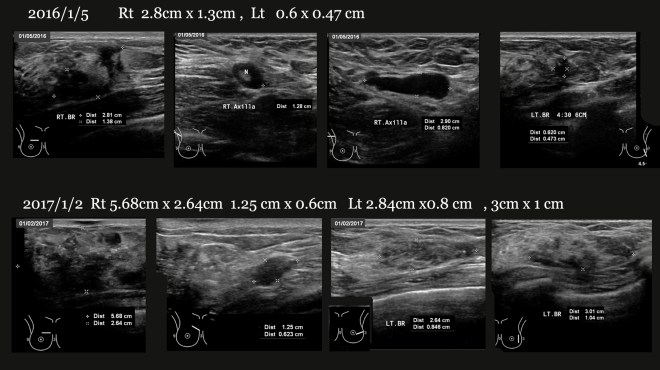

이 환자는 초기 양측성 유방암을 발견하였다. 크기는 우측에 약 28x14mm 정도 약 3cm 정도의 종양과 더불어서 주위에 미세 석회화된 부분이 쫙 깔려 있었다. 우측도 7mm, 6mm 정도의 1cm 미만의 종양과 더물어서 미세 석회화가 주변으로 번져 있었다. 또한 우측 겨드랑이쪽으로 여러 개의 림프절이 커져 있었다. 림프절은 전이성 암으로 판명이 되었고, 특별히 뼈나 복부에 전이된 흔적은 없었지만, 양쪽의 대퇴골 부위와 치골 부위에 골경화의 소견이 있었다. 당시 MR에서는 조영방식이 달라서 넓게 microcalcification(미세석회화) 된 부분까지 다 포함시켜서 약 8.1cm의 우측 유방과 약 6.2cm 좌측 유방에 병변을 이야기 하였다. 우측에 유방 외에도 겨드랑이(액와)와  쇄골하에 림프절쪽으로 검은 점들이 조영이 증가된 영상이다.

우측에 보이던 28mm x14mm의 종양은 34mm x 14.6mm로 커졌고 왼쪽 유방에 보이는 두개의 종양은 크기가 각가 7.6mm와 6.2 mm(2017/1/21sono)에서 6.3mm와 14.5mm로 하나는 1.3mm 정도가 줄었고 나머지 하나는 7.3mm 정도가 늘어났다.

환자는 1년 만에 초기의 오른쪽 28mm x 14mm의 종양이 57m x 26mm 정도로 커졌고 좌측의 종양도 4시 방향의 0.7cm가 3cm 정도로  0.6 cm가 1.2cm로 커지고 그밖에도 자잘한 종양이 더욱 많이 생겼고 림프절도 역시 악화되었으며 유방은 염증성 상태로 부풀어 올라 두꺼워졌다. – 대략 어림잡아서 말하면 초기 오른쪽의  3cm 정도의 종양이 1년 사이에 6cm 가량으로 늘어났고 좌측의 1cm 못미치는 종양이 3cm 정도 또 6mm가 12mm로 늘어났다고 생각할 수 있다. 또한 CT의 결과로는 흉추뼈와 척추뼈의 여러 군데에 종양이 전이가 된 것으로 판명되었다.

# 위의 초음파사진에 좌측의 3cm 2.8cm의 종양은 양약을 시작하고 나서 10일 뒤인 2/10 일자 본원 의뢰 방사선과에서 측정했을 때는 벌써 현격히 줄어들어서 2/10일 초음파에서는 각기 10mm /11mm 정도로 차이가 보였다. 그래서 아래에 초음파 비교에서는 약간의 차이를 보인다.